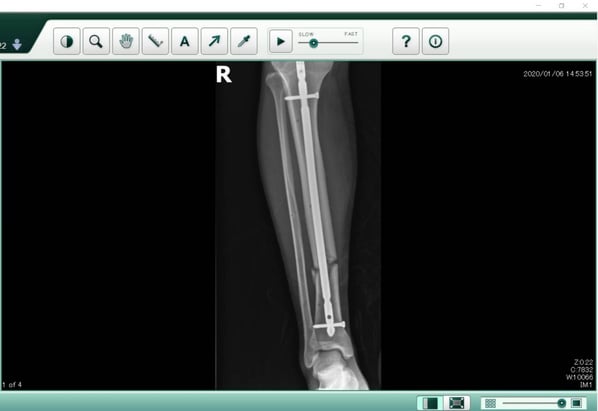

คุณคิดว่าขาหักดามเหล็ก ควรได้เงินเท่าใด

ถ้าคำตอบของคุณคือสองสามแสนก็แจ่มแล้ว

คุณคิดผิดเพราะเคสนี้ได้ 700,000 บาท ครับ